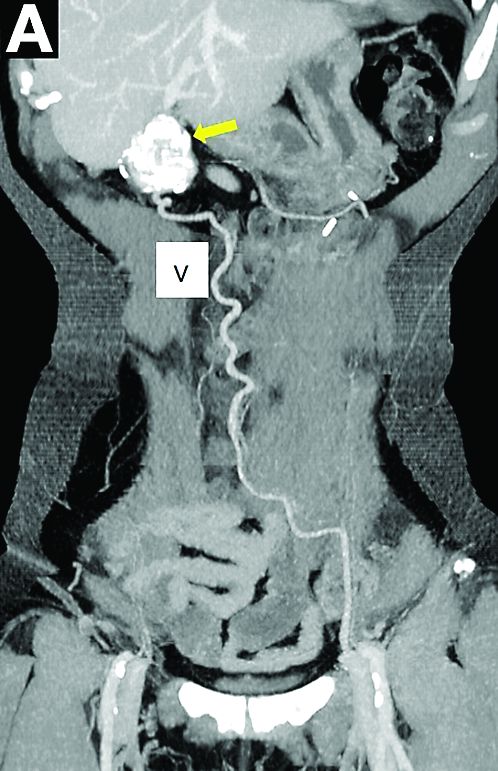

A laparoscopic resection of this mass was performed because of the risk of spontaneous hemorrhage linked to the dense tumoral vasculature and the lack of formal histologic diagnosis. During the procedure, the surgeon observed a cystic mass attached to the ligamentum teres between the liver and the umbilicus. At pathologic examination (Figure B), a well-circumscribed largely cystic mass, with a fibrous and calcified shell and hemorrhagic modifications (arrow) was observed.

Histologically (Figure C), the fibrous wall contained many large vessels and a small cellular area (star). This area consisted of small nests of moderate-sized monotonous clear cells with normochromatic ovoid nuclei. There was no nuclear atypia and no mitosis. The tumor exhibited an elaborate network of small capillaries. Tumor cells expressed the melanocytic marker HMB45 and smooth muscular actin.

Cystic and calcified PEComa of the ligamentum teres

PEComas are tumors derived from epithelioid perivascular cells that typically coexpress smooth muscle and melanocytic markers. The family of PEComas includes angiomyolipoma, clear cell “sugar” tumor, and lymphangioleiomyomatosis. Some of these tumors may be associated with tuberous sclerosis complex. PEComas of the ligamentum teres (also called in this location “clear cell myomelanocytic tumors”) are rare, but the ligamentum teres location is the most classic in children. Thirteen cases have been reported in the literature, within or in the immediate vicinity of falciform ligament/ligamentum teres.1-3 There was a marked female predominance with a mean age of 20 years (range, 3-54 years), a mean size of 8 cm (range, 5-20 cm), and a significant risk of metastasis (3 of 13 cases). Many of the lesions were calcified and had hemorrhagic and cystic alterations.